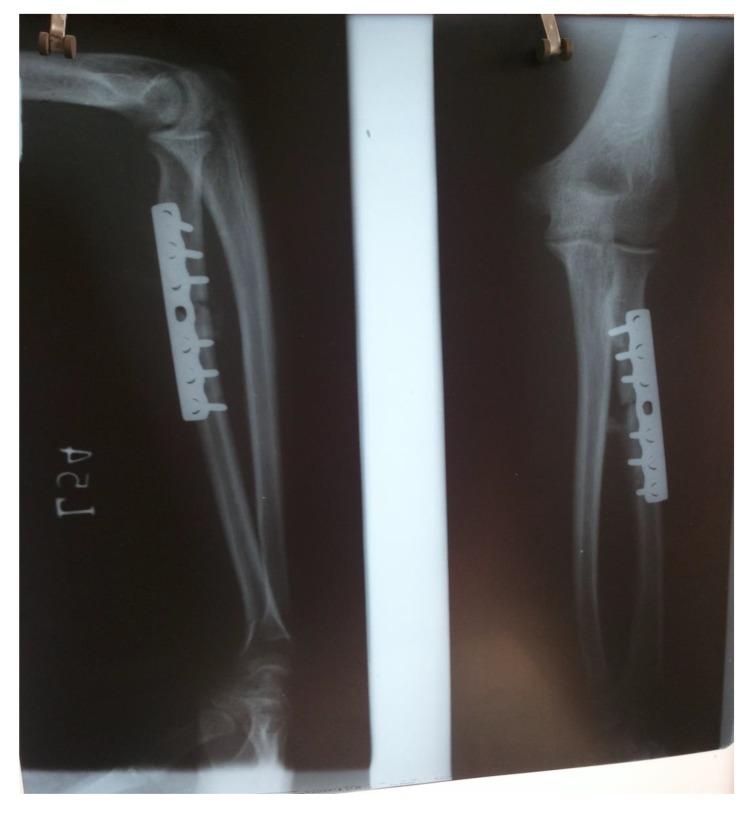

CASE PRESENTATION

We are reporting a case of a young adult male who was operated for proximal one-third radial shaft fracture at some peripheral centre by Open Reduction and Internal Fixation (ORIF), but came to our centre on the fourth post-operative day with complaints of painful restricted movements of the elbow joint. On careful look at the postoperative x-ray, radial head was found to be dislocated. Radial head dislocation was reduced under general anesthesia and at 2 years follow up, patient fracture has fully united having good functional outcome.

我们报告一例年轻成年男性病例,该患者在某外周中心因桡骨近端三分之一骨折接受切开复位内固定术(ORIF),但术后第四天因肘关节疼痛性活动受限前来我院。仔细查看术后X线片发现桡骨头脱位。在全身麻醉下对桡骨头脱位进行了复位,随访2年时,患者骨折已完全愈合,功能恢复良好。